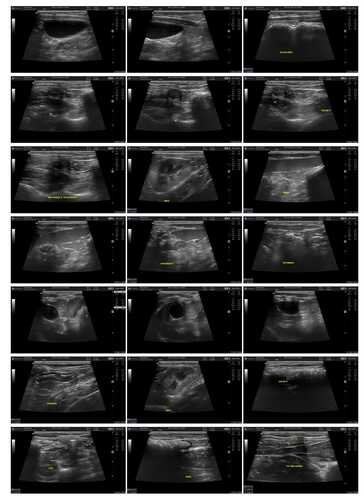

Oi, pessoal! Eu sou o Tico e nasci um gato pirata e criptorquidio. Nasci com um olhinho só funcionando e com as bolinhas ectopicas no abdômen. E agora preciso fazer duas cirurgias muito importantes pra melhorar minha qualidade de vida: castração testicular ectópica abdominal e enucleação para retirar o meu olhinho. Por serem duas cirurgias de risco, os custos são um pouco mais alto que o normal, quem puder ajudar com um pouquinho, ou compartilhando para mais pessoas, me deixaria muitoooo agradecido!

(Essa vakinha é para angariar fundos para poder realizar essas 2 cirurgias, e eu poder me tornar um gatinho pirata e saudável, dessa vez caolho e sem problemas nas bolinhas :)